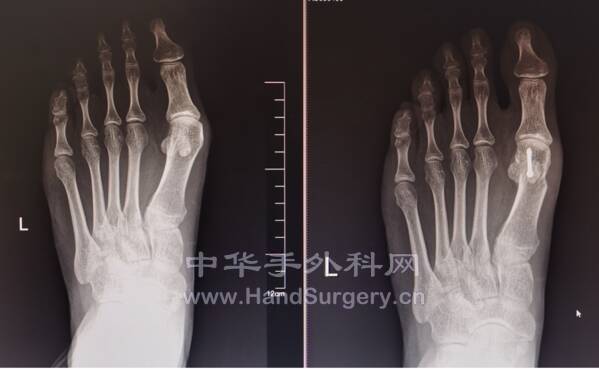

同道讨论的多指畸形

是三节拇指,还是肥大骨骺

mmexport1635424534759.jpg

mmexport1635469017018.jpg

讨论结果:肥大骨骺

术式设计:赘生指切除,肥大骨骺内楔形截骨

确定是不是三节拇指的方法:

1根据间隙大小,两侧拇指拍片对比

2被动活动,有无关节活动度

3可以在C型臂下或者拍被动屈曲位侧位片

4牵引下拍片对比间隙有无增宽

从指横纹的对应位置也可以大概判断有几个关节

指横纹就是皮肤关节的外在表现

请教田晓菲主任,她的经验是肥大骨骺的病例数要多于三节拇病例数

这个病例她很确定是肥大骨骺

建议做骨骺内楔形截骨